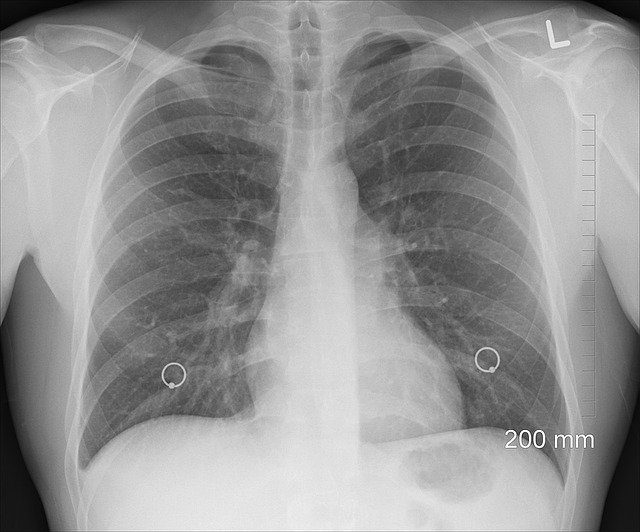

폐암 진단방법

폐암 진단 방법에는 다양한 검사가 있고요. 폐암으로 의심되는 증상이 있을 경우 흉부 x선 촬영, 흉부 CT촬영, 기관지 내시경 검사, 객담검사 등을 이용해서 폐암인지 가부를 확인해 보는 것이 좋을 거예요.